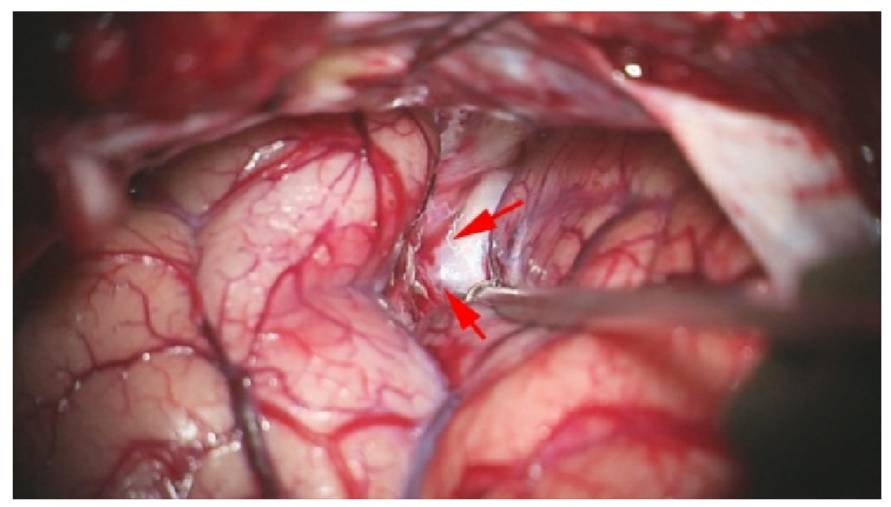

图5. 传统的侧裂分离就是指打开侧裂的前1/3(包括侧裂茎干,近端侧裂:颈内动脉分叉和三角部皮层之间)也被称之为前支,暴露M1和M2内侧2cm的部分。上图展现了传统的侧裂分离范围和程度。箭头所示为经侧裂入路抵达后交通动脉瘤颈部的情况。